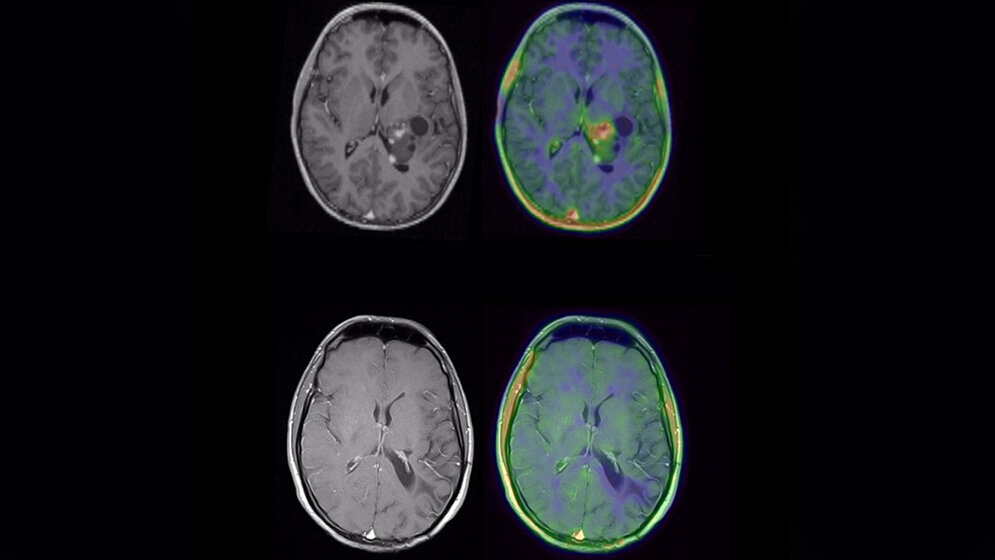

MRT eines Patienten mit Glioblastom vor (oben) und nach (unten) molekularer neuropathologischer Diagnostik und zielgerichteter Therapie.* © UKR

*Ergänzung zur Abbildung:

MRT eines Patienten mit Glioblastom vor (oben) und nach (unten) molekularer neuropathologischer Diagnostik und zielgerichteter Therapie. Die Wilhelm Sander-Therapieeinheit NeuroOnkologie ermöglicht neben einer gezielten Diagnostik auch die personalisierte Behandlung von Patienten mit Hirntumoren.